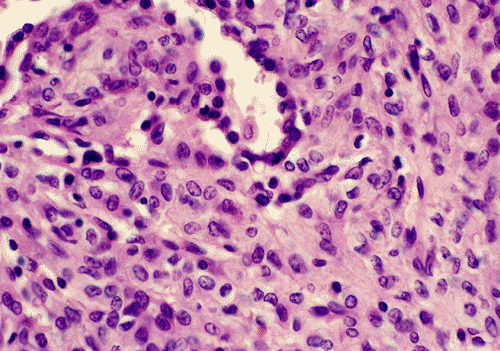

Panel A shows features of the periphery of the tumor that interfaces with the non-neoplastic lung parenchyma. Many choloesterol clefts are present and probably due to resolved hemorrhage. Panel B shows the periphery of the tumor which gives a papillary type of architecture although a real fibrovascular core is absent. Panel C shows the details of these areas. The lesional tissue appear to be composed of solid sheets of mononuclear cells with amphophilic cytoplasm. The cell border is quite clear in some areas but no intercellular bridges or keratinization is present. The surface of the solidly packed cells are lined by a single layer of cuboidal mononuclear cells. The papillary-like structures that are typically seen in the periphery transform into solidly packed tumor cells at the center of the lesion as illustrated in Panel D. Sclerotic changes is also present at the center of the lesion as illustrated in Panel E.

Microscopically, sclerosing hemangiomas have two salient histologic features: marked proliferation of sclerotic, small blood vessels and dual population of mononuclear cells with pale or eosinophilic cytoplasm and pnemocyte-like cuboidal cells. The interplay of these two components generates four recognizable patterns, namely, papillary, solid, hemorrhagic, and sclerotic.  The sclerotic pattern does not usually occur as a pure pattern but accompanies the three patterns. The center of the tumors tends to be more sclerotic. In the sclerotic areas, the collagen is dense and the tumor cells are sparse. In the papillary tumor, the periphery of the tumor has papillary structures lined by eosinophilic cuboidal cells that resemble the alveolar pneumocytes. These cells may continue with the surrounding non-neoplastic alveolar lining cells. There is often a transition of papillary pattern to broad areas of medium-sized, round or polygonal cells with pale eosinophilic or clear cytoplasm. The nuclei are usually oval, with fine chromatin and occasional nucleoli. The solid pattern is composed predominantly of solidly packed tumor cells without significant papillary component. The hemorrhagic pattern appears hemangioma-like and is associated with hemorrhage. A mixed pattern is seen in most sclerosing hemangiomas. Histologic changes secondary to the hemorrhage including hemosiderin-laden histiocytes, cholesterol clefts, and calcifications are common. Presence of tumorlets, areas with neuroendocrine features and foci of mucin production have been described as accompanying findings. The histological features are usually specific enough to allow rapid diagnosis.